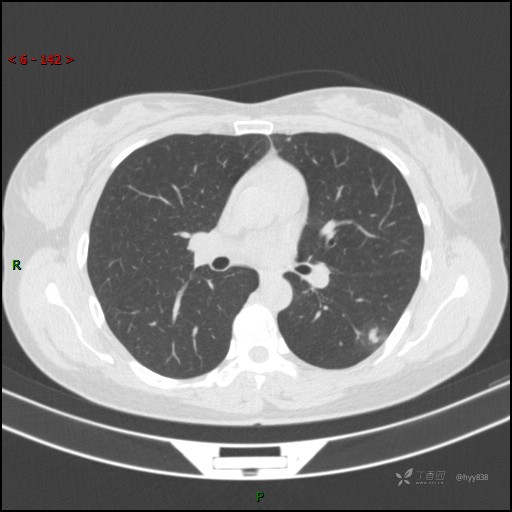

胸膜下“煎鸡蛋征”,感染 VS 炎症 VS 肿瘤,挑战有你---结果公布~

患者性别:女

患者年龄:46岁

简要病史:干咳半月伴左胸部不适

辅助检查:CT

临床诊断:结节

讨论:病变性质?